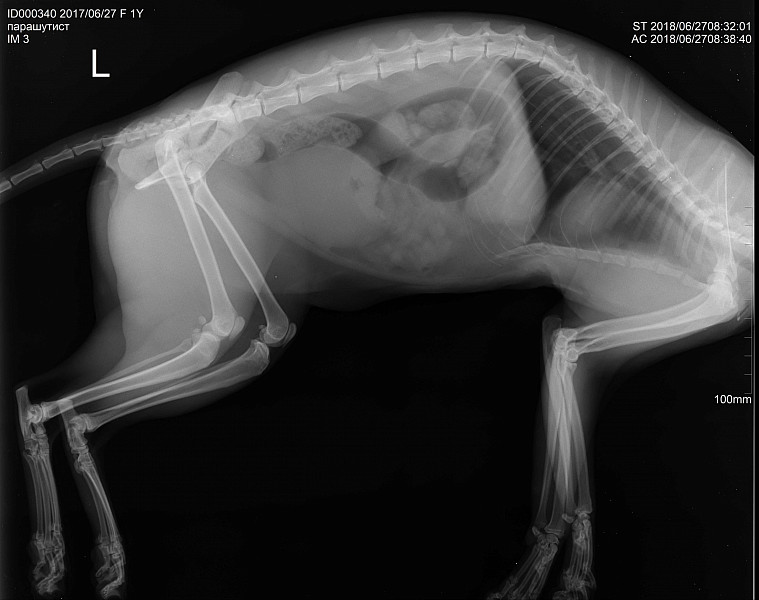

Рентгеновские снимки анатомии собак: строение и здоровье